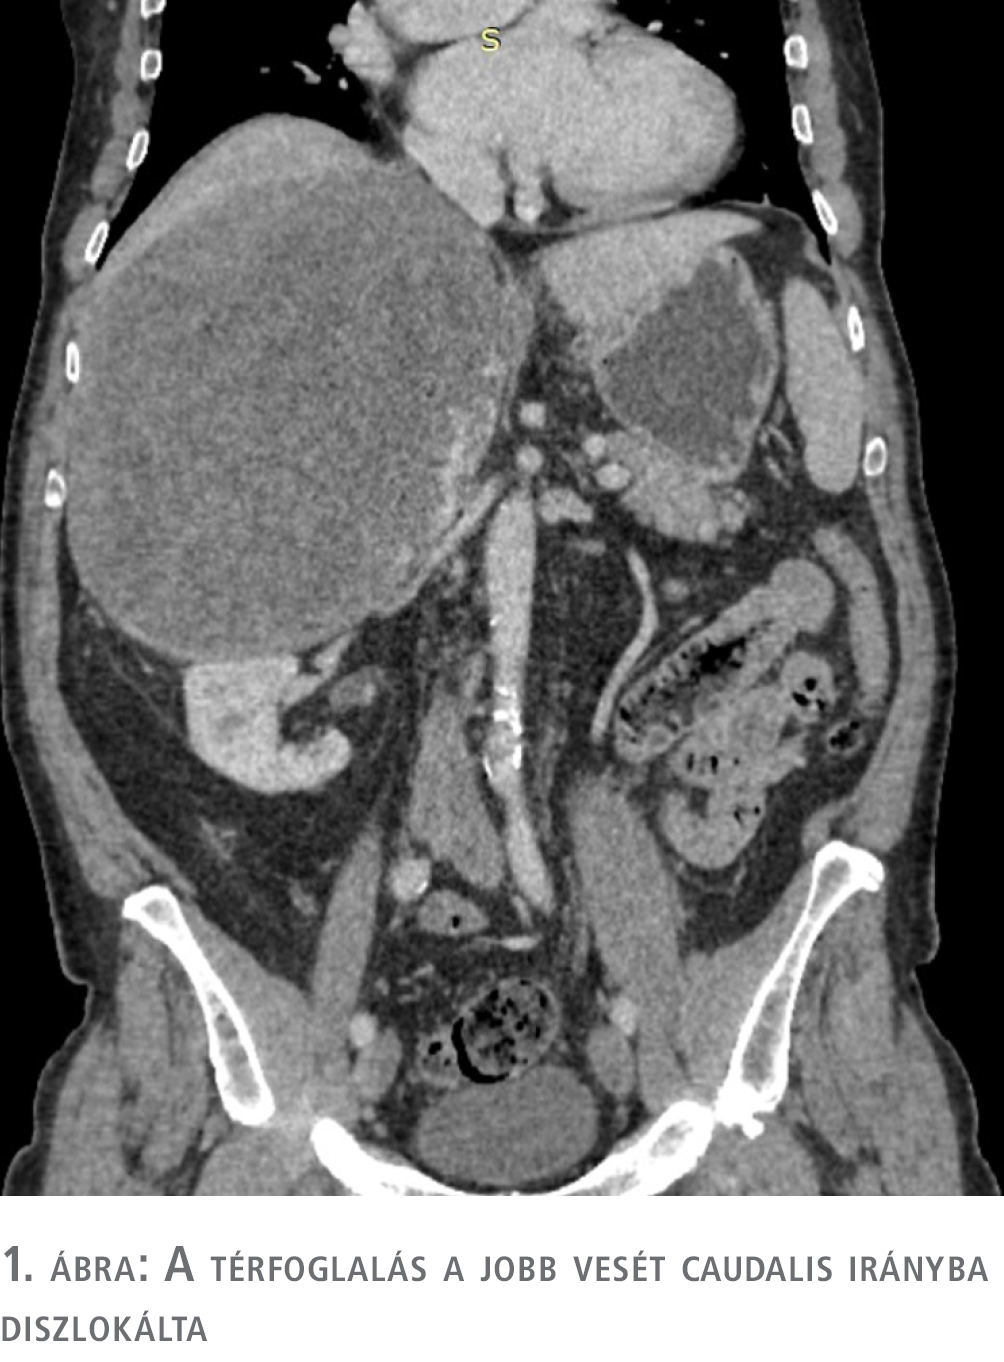

Hasi ultrahangvizsgálat során a máj jobb lebenyének vetületében 16 cm-es inhomogén képletet észleltek, amelynek pontosabb megítélése végett ambuláns CT-vizsgálatot javasoltak. Az elvégzett CT bizonytalan eredetű (máj- és mellékvese-eredetet is felvetett) és malignitású, 18 cm legnagyobb átmérőjű, szélein halmozó, meszesedéseket is tartalmazó képletet írt le.

A CT eredménye alapján a szakrendelőből a beteget sürgősséggel az endokrinológiai osztályra utalták további kivizsgálás céljából. Az endokrinológiai osztályos kivizsgálás során ismét CT-vizsgálatot végeztek, amely a térfoglalás májeredetét elvetette, és halmozási dinamikája alapján elsősorban adrenocorticalis carcinomának véleményezte (1–4. ábra). A hormonprofil alapján hormontermelésre utaló eltérés nem igazolódott. ACTH-, DHEA-S-, kortizol-, CgA- és vizeletmetanefrin-szintek meghatározása, valamint negatív eredményű dexametazonszuppressziós teszt történt. A vizsgálatok és a klinikai kép alapján hormontermelő tumor nem igazolódott. Biopsziát nem végeztek, tekintve, hogy terápiás konzekvenciája nem lett volna sem malignus, sem malignitás nélküli eredmény esetén: a terime mérete alapján malignitási potenciálja nagy, ily módon műtéti ellátása csak malignusnak tekintve történhet.

A máj balra diszlokálódott, a jobb cranialis szegmentumai elsorvadtak, a térfoglalás a vena cava inferiort felemelte és komprimálta, a vesét caudalis irányba diszlokálta. A máj mobilizálása után a terime fluktuáló részletéből intraoperatív citológiai mintát küldtünk, amely a vérből alakos elemeket és kevés histiocytát tartalmazott, így malignitást sem kizárni, sem megerősíteni nem tudtunk, így a térfoglalást továbbra is potenciálisan malignusnak tekintve, onkológiai-sebészeti elvek alapján in toto eltávolítás mellett döntöttünk (6. ábra).